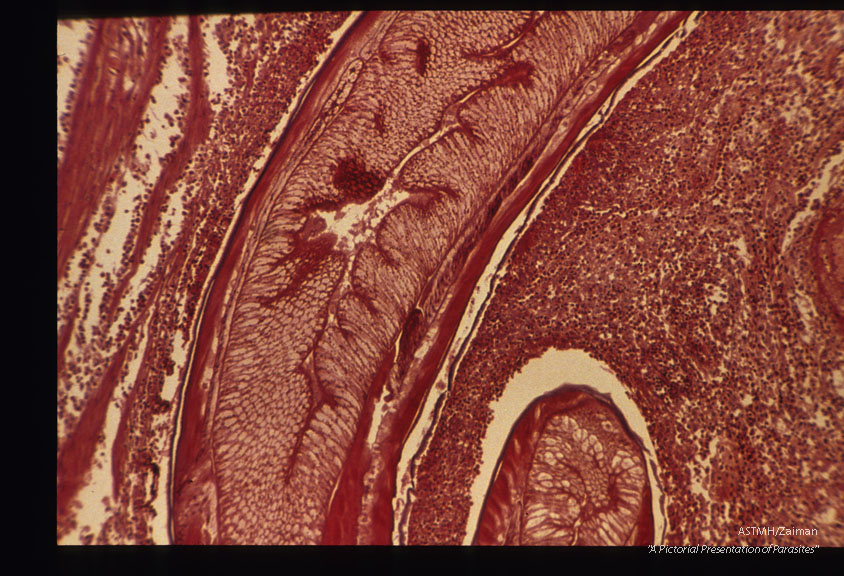

Low and high power magnifications of worm in human stomach wall. Case from Holland.

Anisakis

Description: Low and high power magnifications of worm in human stomach wall. Case from Holland.